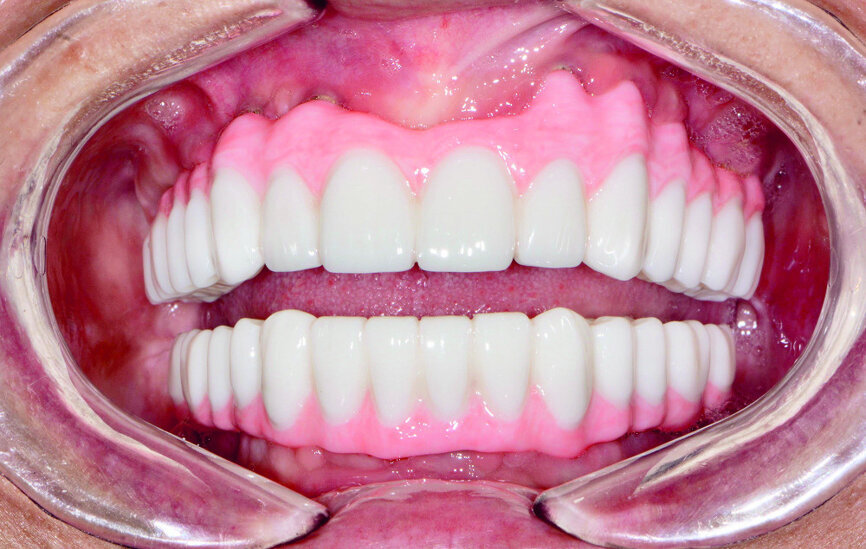

Quatre mois plus tard (Figs. 17 et 18), les piliers de cicatrisation de l’arcade maxillaire ont été désenfouis par une technique chirurgicale, puis les tissus ont été soigneusement refermés. Après la cicatrisation, soit environ deux à trois semaines plus tard, des coiffes d’empreinte ont été mises en place sur les implants coniques Hahn et des empreintes ont été prises au moyen d’un porte-empreintes fermé et d’un matériau en polysiloxane de vinyle (Panasil, de Kettenbach). Un enregistrement de l’occlusion a également été réalisé (Futar, de Kettenbach). Les prothèses immédiates étant bien adaptées et satisfaisantes selon l’avis de la patiente, des répliques ont été envoyées au laboratoire aux fins de concevoir les restaurations définitives. Le laboratoire a utilisé les empreintes pour couler et scanner des modèles en plâtre-pierre, créer une image numérique des arcades de la patiente sur lesquelles les modèles des piliers personnalisés, et des restaurations à sceller ont été conçus. Les piliers personnalisés en titane Inclusive ont été fabriqués avec les composants du sourire en polyméthacrylate de méthyle (PMMA) correspondants.

La patiente est revenue pour une évaluation clinique du modèle prothétique. Les piliers personnalisés ont été mis en place à l’aide de guides de positionnement en acrylique, fournis par le laboratoire pour faciliter l’orientation adéquate pendant l’insertion (Fig. 19). Grâce à la précision de la technique de conception numérique, l’ajustage des piliers personnalisés s’est révélé parfait et définissait des limites marginales positionnées exactement, ou à une distance négligeable de la surface gingivale. Cette précision a fortement simplifié l’élimination de l’excès de ciment des limites marginales et illustre les avantages des piliers produits en CFAO.

Les composants du sourire en PMMA ont été ajustés sur les piliers personnalisés et de légères modifications ont été apportées pour parfaire le rebord marginal de la gencive, la longueur des dents et l’occlusion (Fig. 20). Un enregistrement occlusal a été réalisé au moyen des bridges conçus pour l’essayage. Les composants du sourire en PMMA ont été retournés au laboratoire en même temps que les photographies, l’enregistrement occlusal et des instructions concernant des modifications mineures, notamment une réduction de la limite marginale gingivale de la prothèse mandibulaire et un rehaussement de la limite marginale gingivale de la prothèse maxillaire. Le laboratoire a scanné les bridges en PMMA, ajustés au cours de l’essayage, a réalisé les modifications demandées sur les modèles prothétiques, et a fraisé les prothèses définitives dans des blocs de zircone solide BruxZir.

Les restaurations définitives ont été mises en place au cours de la visite suivante et montraient une adaptation, une fonction et une relation inter-occlusale précises (Figs. 21 et 22). Grâce à la phase d’essayage, aucun ajustement des prothèses en zircone monolithique n’a été nécessaire, car les bridges en PMMA avaient permis de définir précisément les modifications nécessaires à l’obtention de la forme et de l’esthétique parfaites. Une dernière radiographie a confirmé l’adaptation totale des restaurations en zircone BruxZir sur les piliers implantaires personnalisés Inclusive. La patiente s’est montrée extrêmement satisfaite de la reconstruction de ses arcades maxillaire et mandibulaire dont le rétablissement de l’esthétique et de la fonction dentaire lui avait rendu confort et confiance.